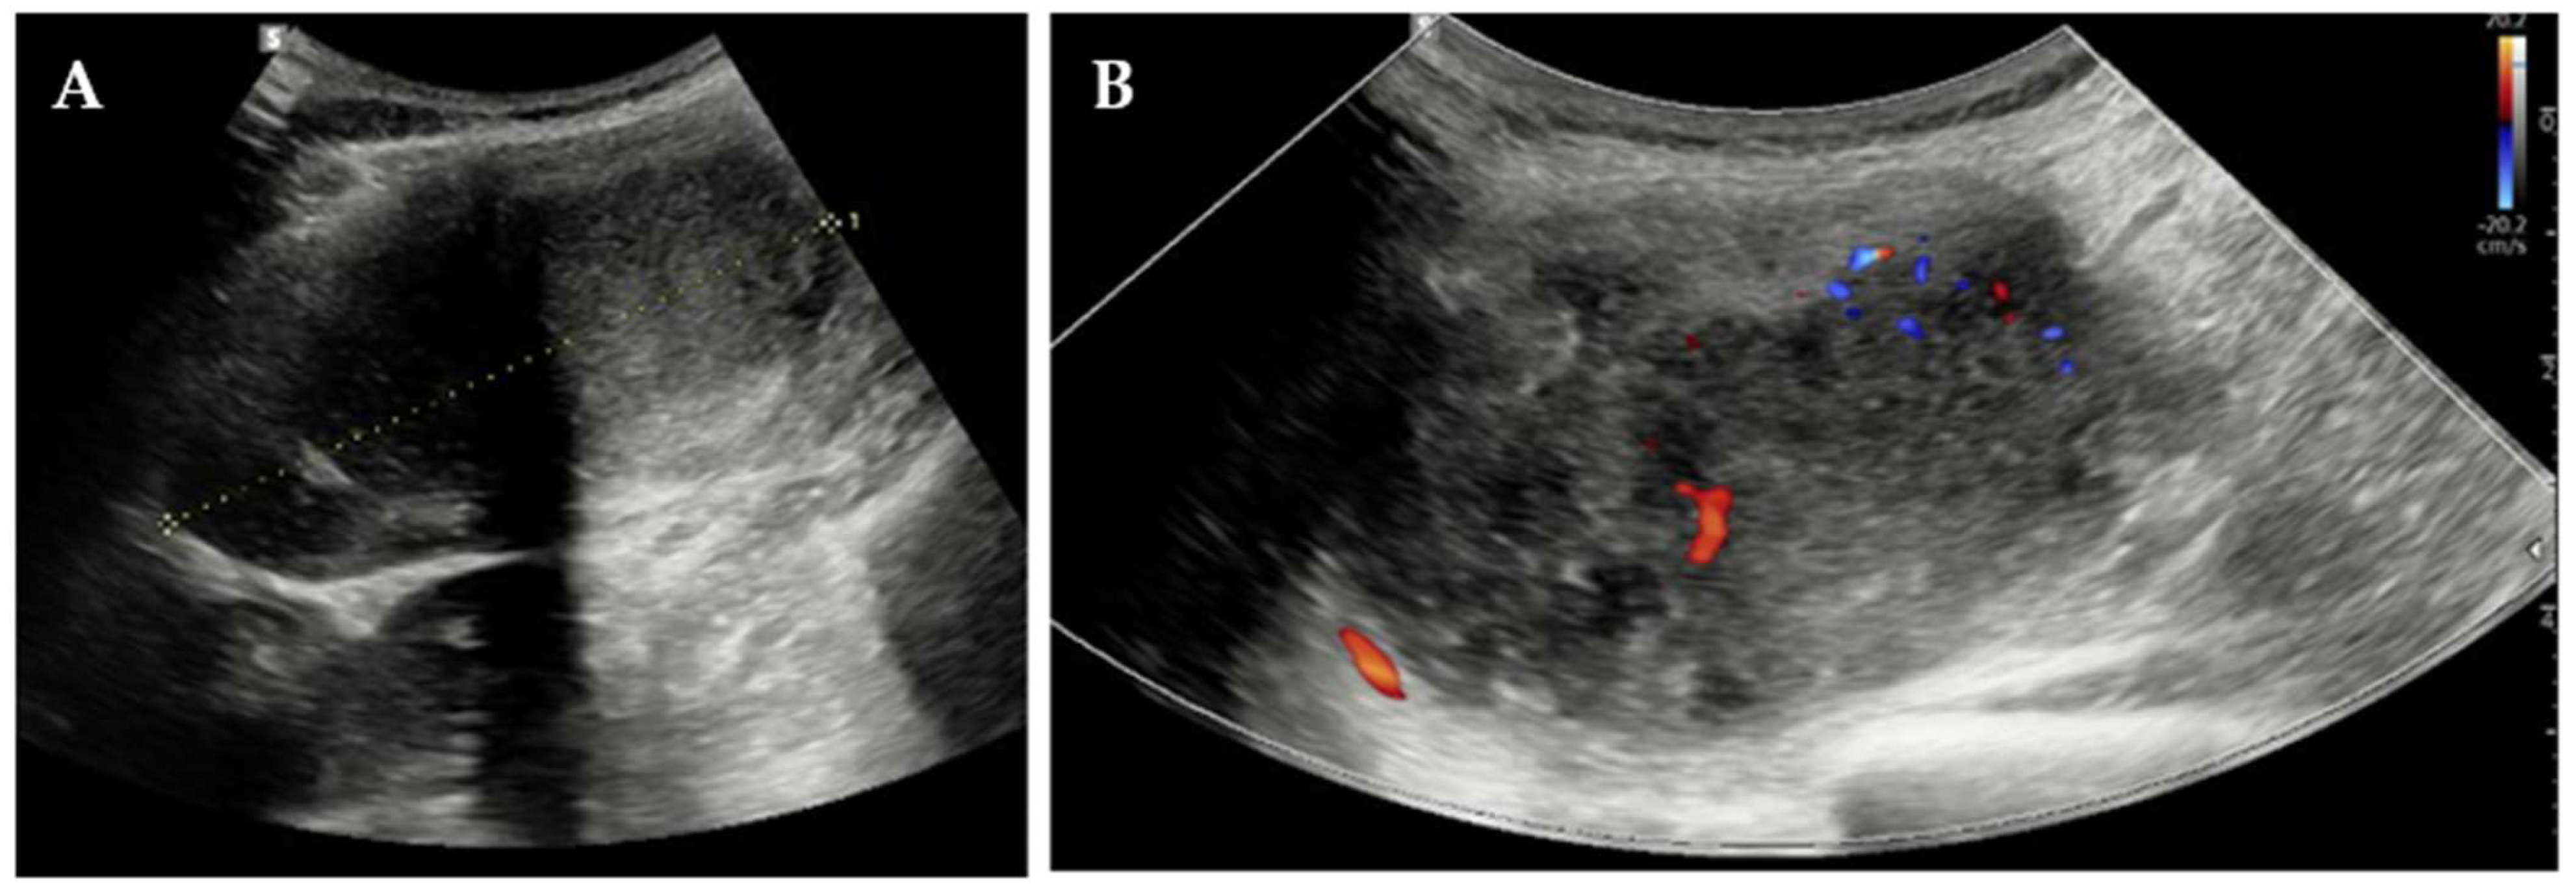

Two months post-partum, CT undertaken elsewhere for febrile pyelonephritis demonstrated marked enlargement of the known abdominal-wall lesion to 70 × 50 × 93 mm, displacing but not invading the right kidney (Figure 2).

Figure 2.

CT scan of the right abdominal wall: coronal (A) and axial (B) view of the abdominal-wall DT.

The mass remained heterogeneous and predominantly hypodense with peripheral enhancement, and it was again interpreted as an endometrioma; residual splenosis nodules persisted (largest 3.3 cm).